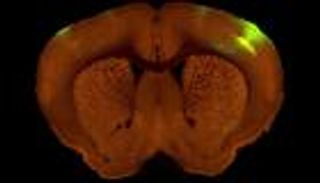

وقالت وزارة الصحة في ولاية فلوريدا إنها سجلت حالة عدوى لالتهاب السحايا والدماغ الأميبي الأولي التي تسببها أميبا أحادية الخلية تُعرف باسم "النيجلرية الدجاجية - Naegleria fowleri".

وتعيش أميبا "النيجلرية الدجاجية" عادة في المياه العذبة الدافئة مثل البحيرات والأنهار والبرك.